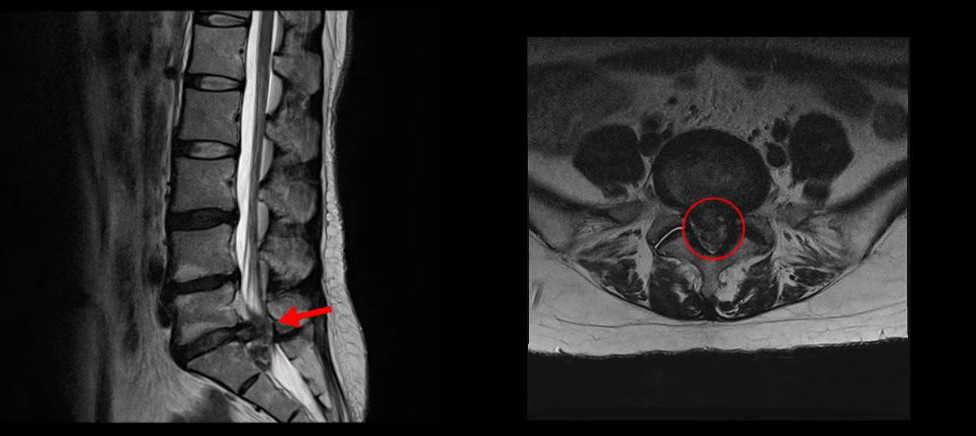

<5-1번 디스크 파열>

이 환자분의 허리 MRI를 보면 5번, 1번 디스크가 매우 심하게 터져 있는 것이 보입니다. 굉장히 심한 허리디스크터짐으로 인해 신경이 있어야 할 곳을 밀려나온 디스크 수핵이 거의 다 차지하고 있는 것을 볼 수 있습니다.

디스크가 심하게 터져서 수핵이 많이 밀려 나오니까 수핵이 위로도 밀려 올라가고 아래로도 흘러내려 있습니다.

축상면으로 보면 수핵이 위로도 밀려 올라가서 신경 공간을 까맣게 차지하고 있는 것이 보입니다.

아래로도 저 밑에까지 흘러내려가 신경 공간을 많이 차지하고 있어서 신경의 형태가 제대로 보이지가 않습니다.

MRI로 이 정도의 심한 파열이 보이면 다리에 마비나 대소변 장애까지도 있지 않을까 의심될 수 있는 상황인데요. 그래서 환자분이 MRI를 찍은 정형외과에서도 대소변 장애는 없는지 확인하였고, 파열이 심하니까 무조건 바로 수술을 해야 한다고 얘기했다고 합니다. 그런데 다행히도 이 환자분은 다리에 감각 마비와 보행 시 힘 빠짐 증상은 있으나, 대소변 장애는 없었습니다.